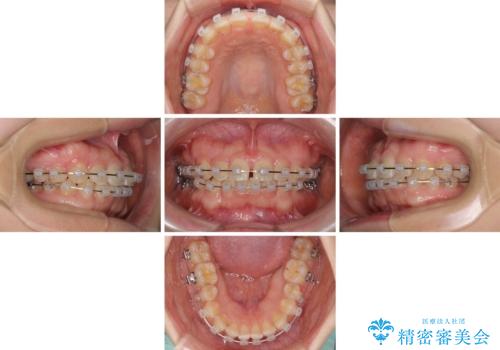

- 矯正装置

- クリアブラケット

- 治療期間

- 1年6ヶ月